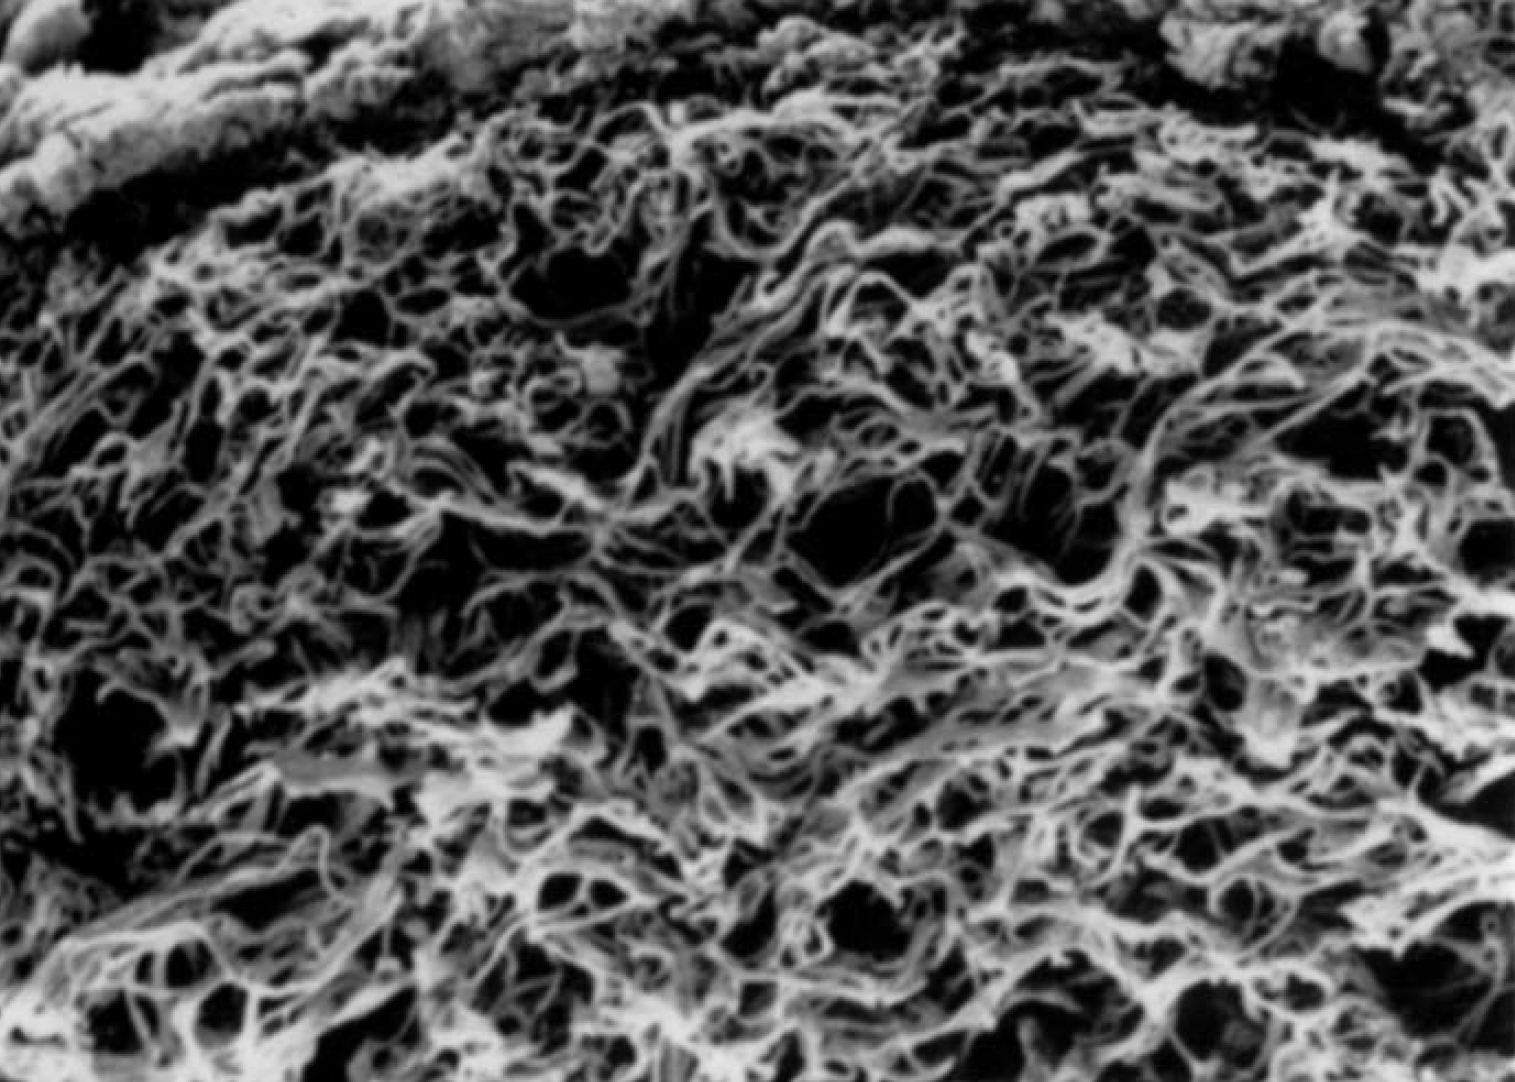

G4Derm Plus Mimics the Native ECM2,7

G4Derm Plus

Scanning Electron Microscopy (SEM) magnification 5,000x and 270x, respectively.